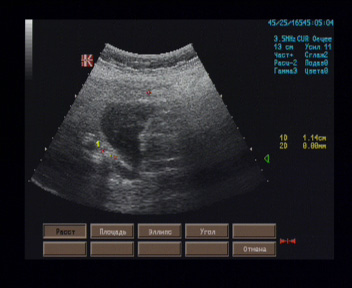

Жёлчный пузырь размерами 91 х 34 х 32 мм, контуры ровные, чёткие; стенка на всём протяжении хорошо контурирована, однородная, толщиной 2 - 4 мм, в проекции кармана Гартмана лоцируется неподвижная гиперэхогенная структура 11 х 7 мм, дающая акустическую тень; на остальном протяжении просвет желчного пузыря свободен.

Эхографические признаки камня в просвете кармана Гартмана жёлчного пузыря, застойного жёлчного пузыря.